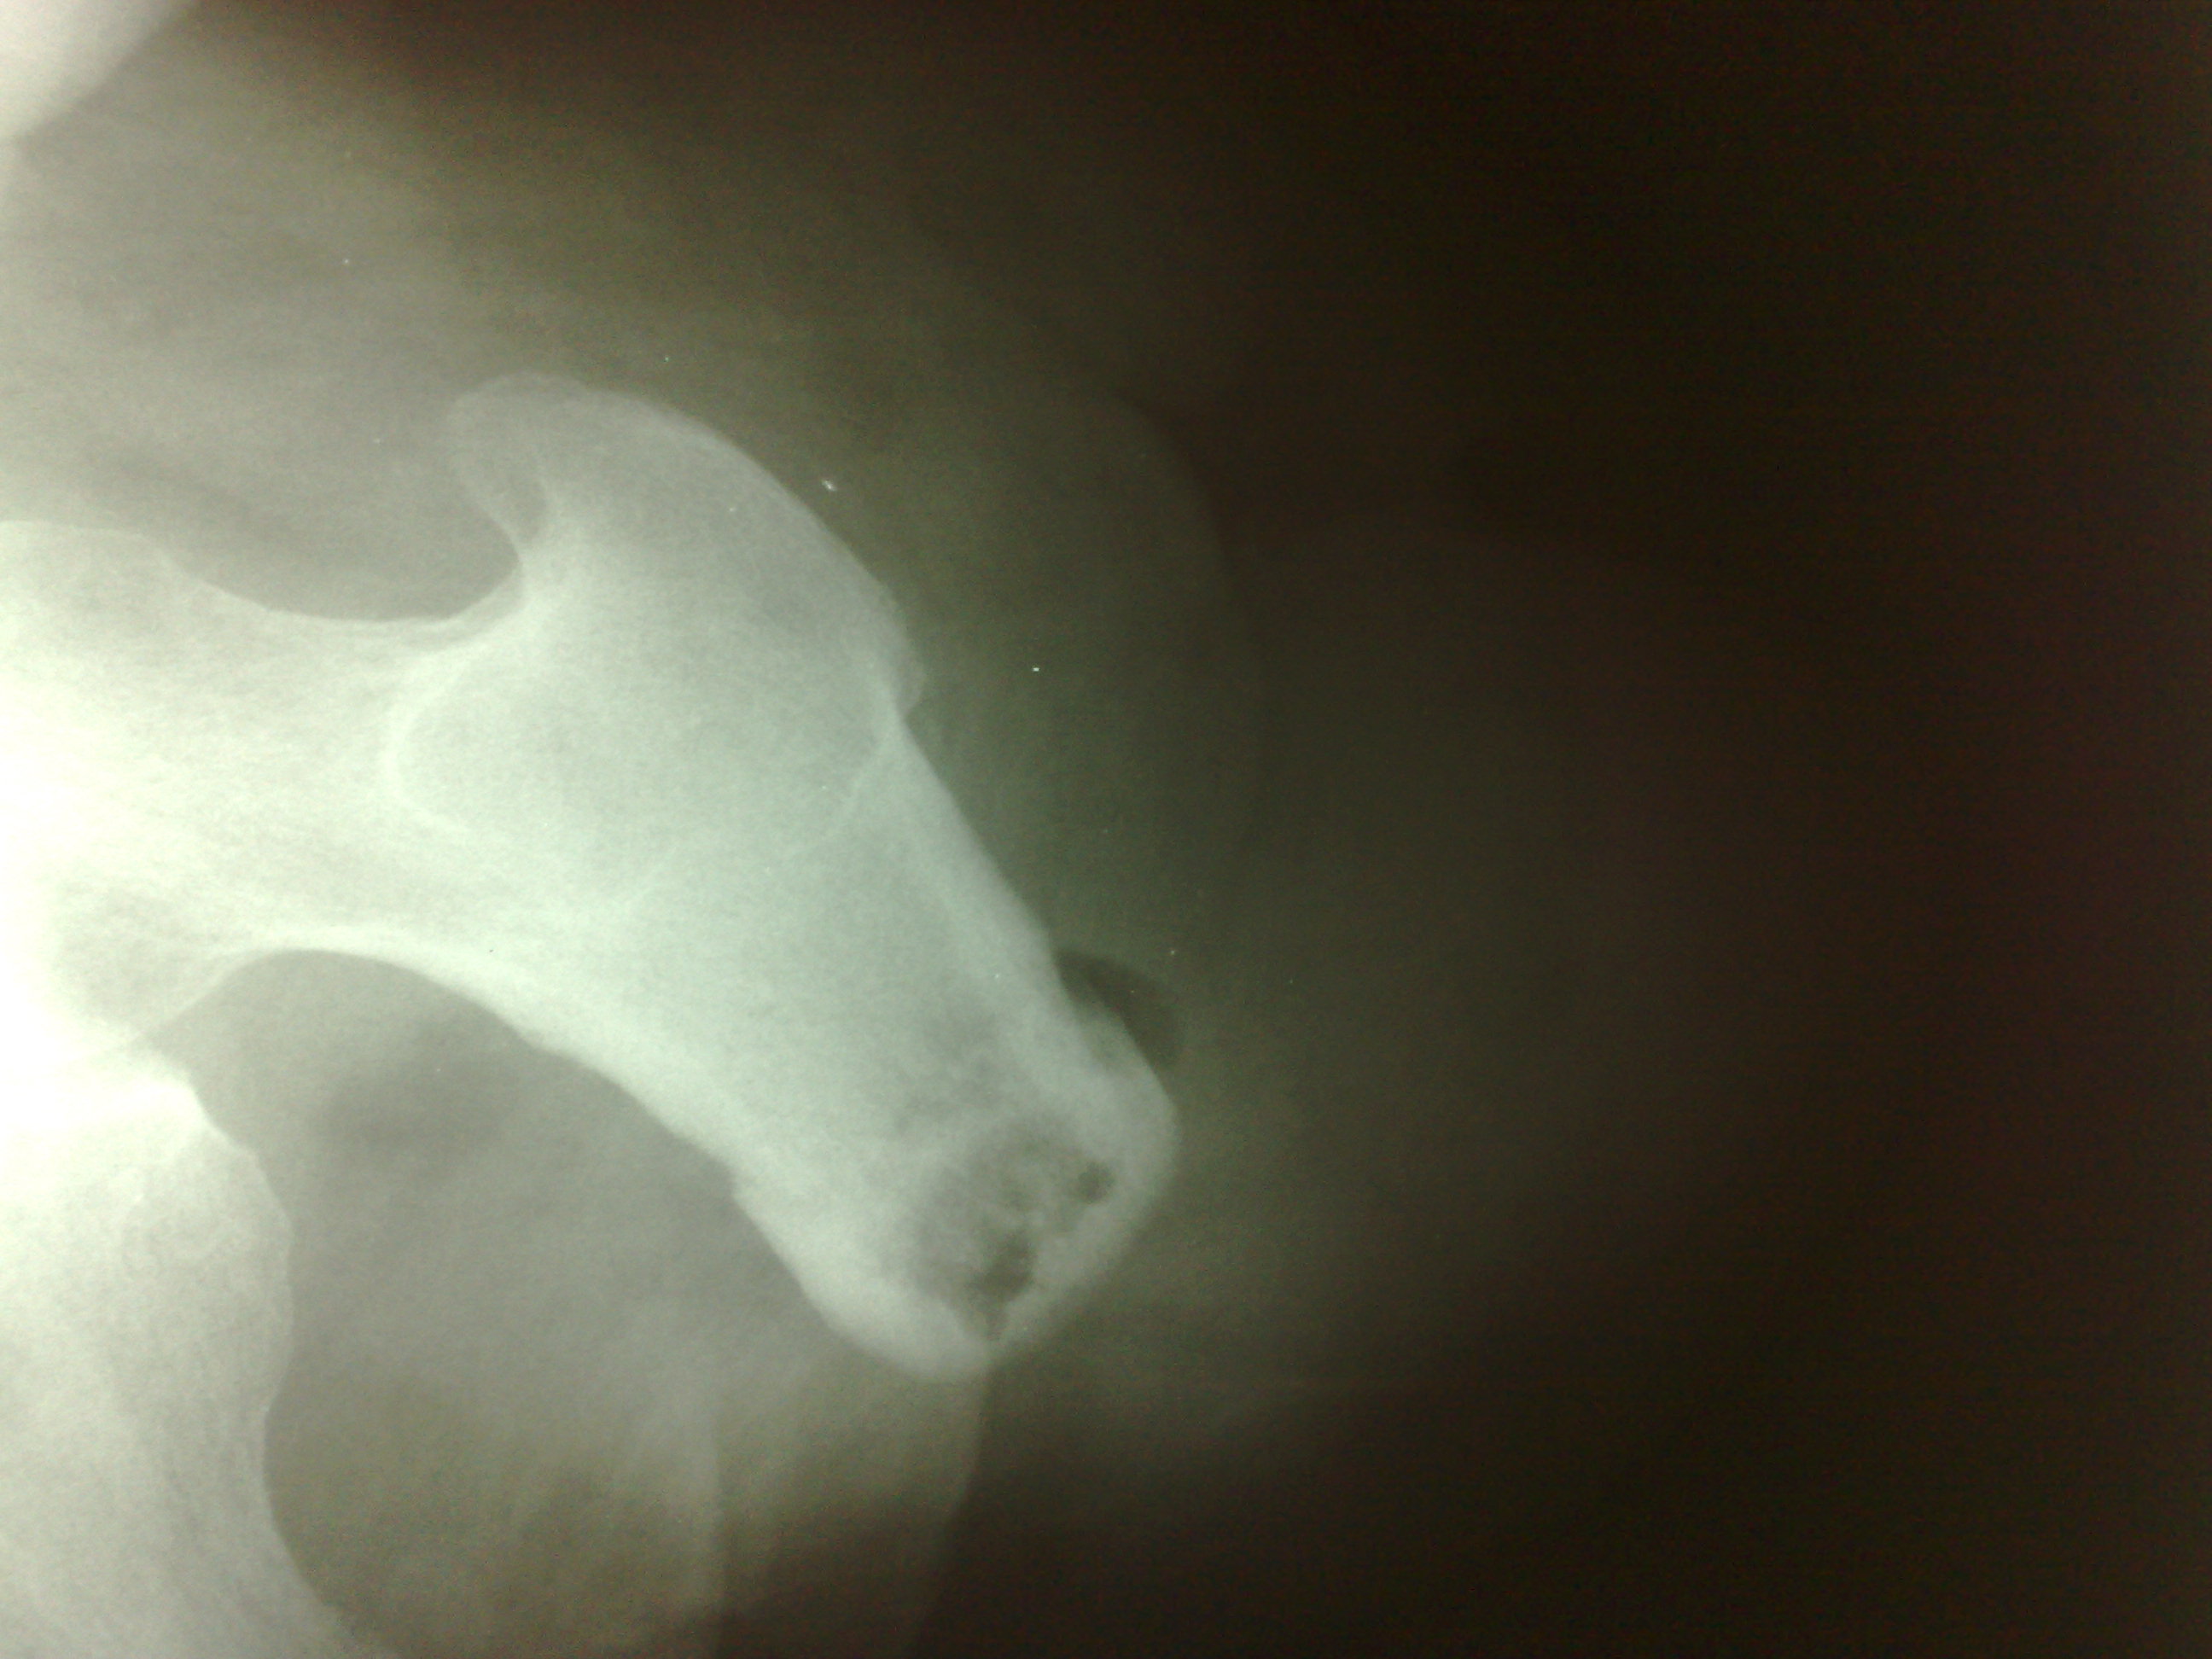

Мужчина средних лет, упал, диагноз: Перфорация культи. В заключении ничего такого страшного я не написала. Приходит хирург и говорит, что у него хр. остеомиелит, как я могла его пропустить. Укажите, пожалуйста, где здесь признаки остеомиелита. Снимки прилагаю:

Наличие газа в мягких тканях видно, признаков хронического миелита (наличие секвестров, костная деструкция, гиперостоз,выраженный периостит) - не вижу. Разве что остеопороз дистального отдела культи... Но не факт, что такая картина обусловлена наличием газа в мягких тканях.

На остеомиелит не похоже. А вот циркулярный (венечный) секвестр может быть. Но это надо выяснять, явно не хватает бокового снимка (лаборантам НЕреспект, все-таки в 2-х проекциях снимать надо).

в доказательство остеомиелита он предлагал внимательнее посмотреть на внутренний контур костно-могзовой полости - что там имеются полости деструкции, а на то, что указано стрелками (утолщение что ли...), ну и еще предлагали посмотреть но костный отпил (он иссек эти полости)

Согласен с переломом. Возможно, с выраженным угловым смещением в перпендикулярной снимку плоскости. Концы отломков образовали якобы "полость просвеления" в дистальном отделе культи.

Он стоит особняком. И имеет не сколько инфекционную/микробную, сколько дистрофическую/нарушение трофики/ м.б. сосудистую природу. Я в таких случаях так и пишу "р-признаки концентрического/цилиндрического/венечного (что понравится) секвестра культи"

Он, обычно возникает, как результат перегрева кости. Очень быстро пилят и не охлаждают опил физраствором из шприца. Сам секвестр формируется довольно долго. То, что представляется вколоченным переломом, это демаркационный вал на границе мертвой и здоровой кости.

Вживую видела 2 венечных секвестра, оба тонкие, действительно кольцевидные, с периостальной реакцией. Здесь нет периостальной реакции, кольцо не просто широкое, но еще и косо-широкое. К хирургу есть вопросы, что же он там на самом деле видел... и что сделал - иссечение края секвестра?...

1.Юрий Андреевич, но я ведь тоже не говорил о "вколоченом" переломе! говорил о переломе (дефекты кортикала с обеих сторон, неровная, зубчастая линия просветления от одного дефекта кортикала до другого...да есть местами участки уплотнения, но не настолько интенсивны, чтобы четко говорить о вклинении).

2. Отрицать изменения структуры в дистальном отделе культи (?) - полость с наличием секвестроподобных включений - не могу, они не свидетельствуют о "нормальности"..они в большей степени характерны для хронического воспалительного процесса.

3. Наличие циркулярного секвестра не оспариваю, но и не утверждаю, что его нет...может все, что мной описано - и есть ОН (к слову - никогда подобное не втречалось ...пока...может этот случай первый